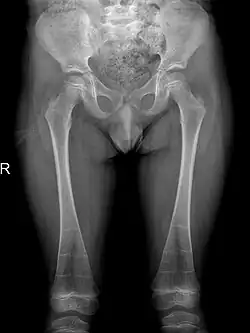

A frontal radiograph showing metaphyseal flaring of both femora[19]

Sclerosis of epiphyses, diaphyses, and metaphyses with increased radiolucency are key characteristics of the disease.[18] In addition, mottled metaphyseal sclerosis and widening are also present in patients.[4][9] Development of irregular patchy sclerosis along the bone can also be identified,[9] as well as metaphyseal flaring evolve towards Erlenmeyer flask deformity with nonuniform patches of sclerosis, which are especially prevalent in older patients.[10]

The metadiaphyses, a portmanteau of the metaphysis and diaphysis,[20] are bulbous and expanded with bowing and relative radiolucency. The expanded regions are also sclerotic and gives the characteristic bone-in-bone appearance.[4]

The occurrence of DSS also leads to deformities of the limbs. 80% of patients reported with abnormalities of the metaphysis such as metaphyseal flaring, radiolucent metaphyses, abnormal metaphyseal trabeculation, which is abnormal trabecula patterns in the metaphyseal region, and epimetaphyseal sclerosis. Other limbic abnormalities include progressive bowing of long bones, which is present in rare cases.[6][7]